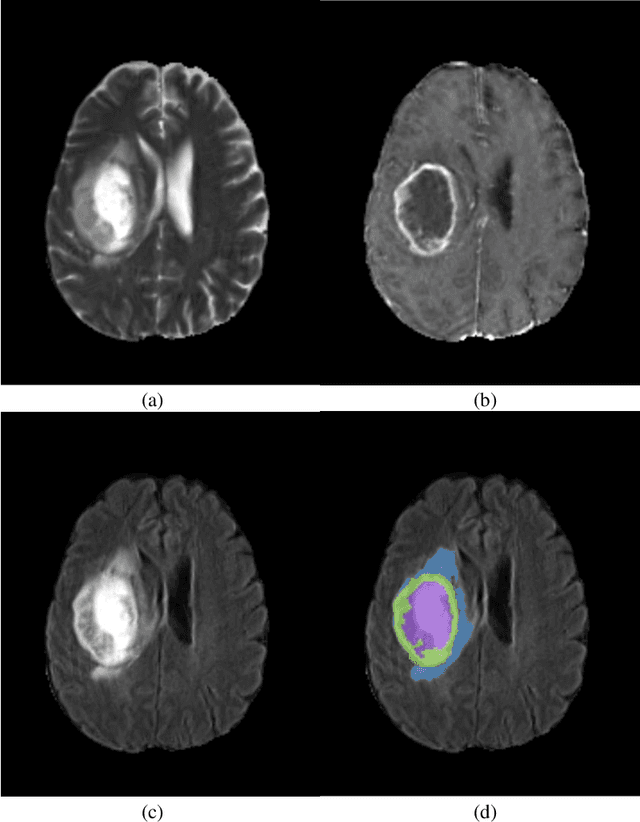

Glioblastomas are the most aggressive fast-growing primary brain cancer which originate in the glial cells of the brain. Accurate identification of the malignant brain tumor and its sub-regions is still one of the most challenging problems in medical image segmentation. The Brain Tumor Segmentation Challenge (BraTS) has been a popular benchmark for automatic brain glioblastomas segmentation algorithms since its initiation. In this year, BraTS 2021 challenge provides the largest multi-parametric (mpMRI) dataset of 2,000 pre-operative patients. In this paper, we propose a new aggregation of two deep learning frameworks namely, DeepSeg and nnU-Net for automatic glioblastoma recognition in pre-operative mpMRI. Our ensemble method obtains Dice similarity scores of 92.00, 87.33, and 84.10 and Hausdorff Distances of 3.81, 8.91, and 16.02 for the enhancing tumor, tumor core, and whole tumor regions, respectively, on the BraTS 2021 validation set, ranking us among the top ten teams. These experimental findings provide evidence that it can be readily applied clinically and thereby aiding in the brain cancer prognosis, therapy planning, and therapy response monitoring. A docker image for reproducing our segmentation results is available online at (https://hub.docker.com/r/razeineldin/deepseg21).